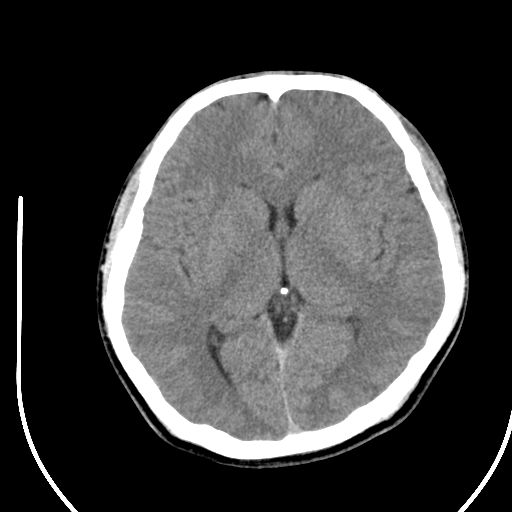

标题: CT28158:男,27Y。头痛数月,左顶叶血管瘤。 [打印本页]

标题: CT28158:男,27Y。头痛数月,左顶叶血管瘤。

考虑左顶叶海绵状血管瘤,建议mr检查。

左侧额叶海绵状血管瘤可能性大;建议行mri检查。

考虑血管畸形,因其周可见水肿,不除外感染性病灶。建议mri检查。